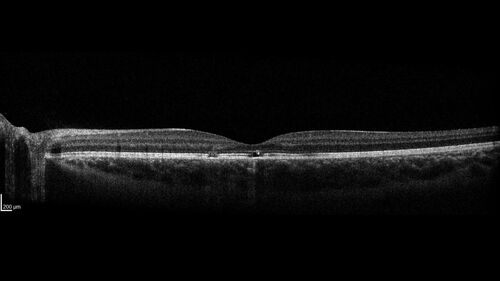

Laser pointer maculopathy

11 year old male When school started the patient noticed that he was having trouble reading and seeing out of both eyes. There are no retinal diseases in the family.

VA OD: sc20/25

VA OS: sc20/40

TP: OD:19 OS:18